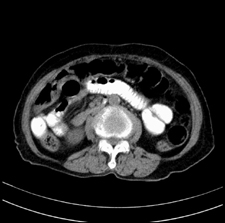

患者,女,75岁。腹痛,体黄5日,膝胸位时腹痛缓解。肝功能明日出来。彩超提示胆总管占位,未见血流信号。心电图提示s-t段改变。患者体质较弱,未能增强。

胆总管多发结石

胆总管多发结石伴肝内外胆管轻度扩张。

胆总管多发结石伴肝内外胆管扩张。